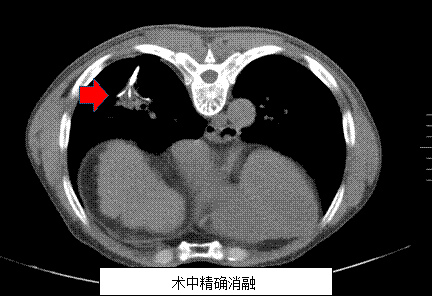

患者姜某因消化道出血在介入科住院时发现右下肺小病灶,经该科肺占位穿刺活检后确诊为支气管肺泡癌。由于患者基础疾病较多并已有腋窝淋巴结转移,外科开胸手术风险极高,且家属不愿行外科手术经。科主任吕军及科内会诊后,决定为患者采用CT引导下肺部肿瘤射频消融治疗。患者射频治疗后复查发现病灶完全消融,肺内无明显出血及气胸,无明显不良反应,疗效非常好,术后第二天患者已能正常活动。

据吕军主任介绍,目前肿瘤介入治疗手段多样,单一方法很难很好控制肿瘤,肿瘤射频消融治疗是一种先进的杀伤肿瘤较多而损害机体较轻的肿瘤微创切除治疗方法。该方法就是将一根细细的射频消融针在影像设备引导下穿刺入肿瘤组织内利用射频热效应使肿瘤组织细胞凝固性坏死的原理而达到消除肿瘤的目的。具有疗效好,创伤小,痛苦小,适应症广等优点,在小肝癌、肺癌等实体肿瘤治疗效果方面,据国外相关文献报道其效果与外科手术切除类似。目前临床应用较多的是:肝癌、肾癌、肺癌、肝脏和胸部的转移性肿瘤。